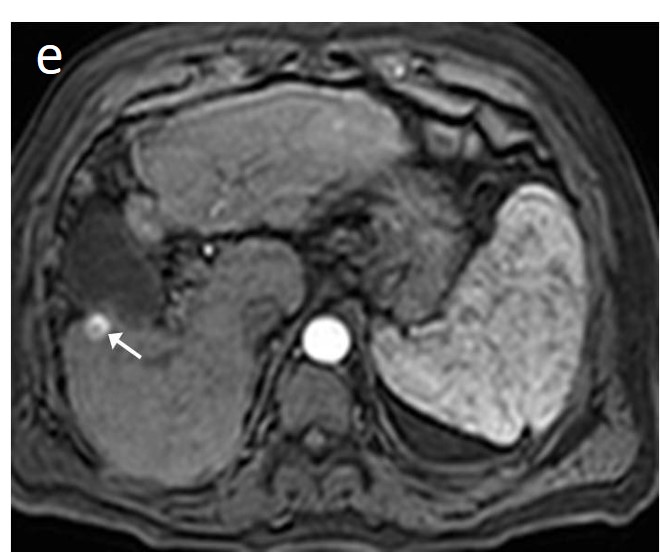

Fatty change is encountered in approximately 40% of early HCCs [143]. With increasing tumor size and histologic grade, fat usually regresses and the percentage drops to 6% in moderately-differentiated HCCs [144], only to increase again in highly de-differentiated tumors. This occurs along with the diminished arterial supply, suggesting a connection between reduced blood flow, hypoxia, and steatogenesis [145]. MRI is superior to CT in detecting fatty change with the use of chemical shift sequences, which show the characteristic signal drop on the opposed-phase compared to the in-phase (Figures 12 and 13). Intratumoral fat can also be used to exclude cholangiocarcinoma, which is also associated with cirrhosis. Nevertheless, the added value of fat identification in a HCC is debatable because, when detected, other more suggestive features (like the vascular pattern) are already present [123].

Figure 13. Sixty-five-year-old man with cirrhosis. On the T2 sequence, a nodular high T2 lesion is vaguely seen (arrowheads) (a). The lesion appears hyperintense on the in-phase image (b) and slightly hypo-intense on the out-of-phase image (arrowheads) (c), suggesting the presence of fat. On the hepatobiliary phase after gadoxetic acid administration, a small nodule with markedly decreased signal (no contrast uptake) is evident in the left aspect of the larger lesion (arrow), suggesting focal de-differentiation in a dysplastic fatty nodule and early HCC formation (“nodule in nodule” sign) (d).

The introduction of hepatospecific contrast media in the 2000s has opened new perspectives in liver imaging. Following their intravenous administration, multiphasic dynamic imaging is performed—similarly to extracellular agents—and subsequently, they are taken up by functioning hepatocytes via specific transporters (organic anion-transporting polypeptide, OATP). Approximately 30% of high-grade dysplastic nodules demonstrate decreased expression of these transporters; the percentage rises to 70% in early HCC, while all poorly-differentiated tumors show decreased or absent expression of OATP transporters [153], leading to low signal intensity on the hepatobiliary phase. More importantly, the decline of OATP expression precedes the typical vascular changes of hepatocarcinogenesis, making the hypo-intensity on the hepatobiliary phase the most sensitive imaging feature for early diagnosis of HCC [125,126,130,154,155]. Typical HCC appears hypo-intense on the hepatobiliary phase and the degree of hypo-intensity has been correlated to histologic grading [156] [157,158]; however, approximately 10% of HCCs appear iso-intense or hyperintense relative to the surrounding liver on the hepatobiliary phase with gadoxetate (paradoxical uptake). The iso/hyperintensity may not be due to tumor differentiation, but rather represents a peculiar molecular/genetic subtype—probably due to genetic or epigenetic alterations—with less aggressive biological features [159,160]. Additionally, it has been shown lately that hyperintensity during the hepatobiliary phase reflects the activation of the Wnt/β-catenin pathway, which, in turn, is associated with resistance to immunotherapy, thereby suggesting that the specific imaging feature (i.e., paradoxical uptake of gadoxetate) could serve as an imaging biomarker [161,162].

When a smaller nodule is seen within a larger nodule, it implies de-differentiation of a cell subpopulation and progression towards hepatocarcinogenesis. The “nodule-in-nodule” sign suggests development of HCC within a dysplastic nodule (Figure 13) and the typical HCC features, such as the wash-in/wash-out pattern or diffusion restriction, are seen in the inner nodule. When numerous foci with different imaging characteristics are seen within a nodule, the appearance is known as a “mosaic” pattern and is usually encountered in large tumors (Figure 12), thereby facilitating the differentiation from cholangiocarcinoma [54].